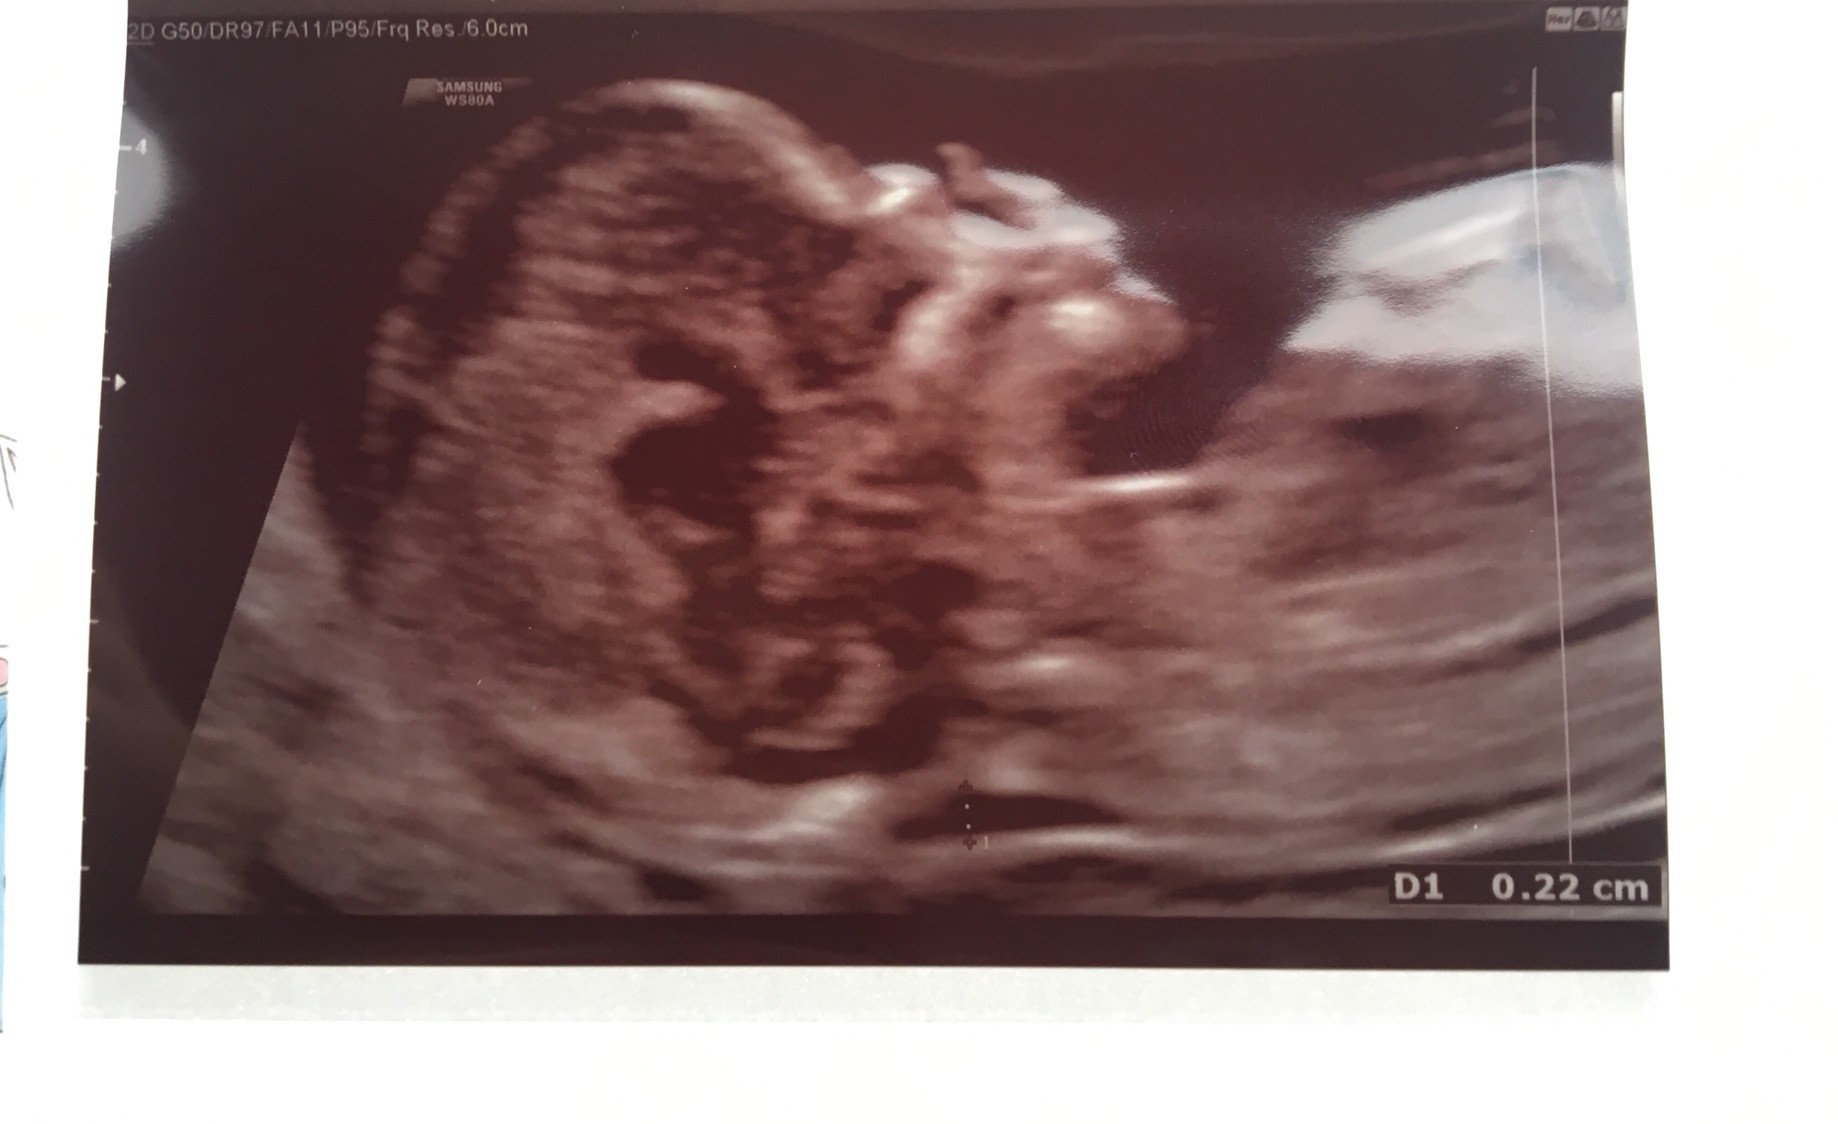

Usg trwało 35 min, pani doktor wszystko dokładnie pomierzyła - mówiła, że wszystko jest książkowo. Widzieliśmy rączki, nóżki, główkę, kręgosłup... Ryzyko wyszło mniejsze niż 1-20000.

Na 90% będzie dziewczynka. [emoji4]

CRL 7.69 cmZobacz załącznik 900591